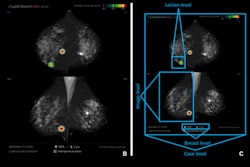

In other AI news, another study this week concluded that an AI model can help detect interval cancers missed by radiologists on screening mammograms. The algorithm was also helpful in localizing these cancers.